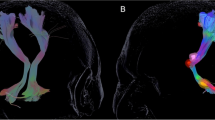

Tractography Delineation by Probabilistic Tracking

The probabilistic fiber tracking detected the NSP, DRTT, and HDP in all 62 hemispheres in the DBS-on state and in 46 hemispheres in the DBS-off state. Figure 3 shows the probabilistic tracking result of one representative patient in two states: (a) DBS-on state and (b) DBS-off state. Overall, the NSP is best reconstructed on the postoperative images, followed by the DRTT and the HDP, which is in concordance with the results by the DT method. It should be noted that the artifacts produced by DBS leads and electrode contacts in and around the STN to some extent lead to signal loss in DTI data, so the fibers between PG and STN cannot always be accurately reconstructed.

Illustration of the NSP, DRTT, and HDP reconstructed by probabilistic tracking method in one representative patient in two states. a DBS-on state; b DBS-off state. STR striatum, THA thalamus, PG precentral gyrus, SN substantia nigra, STN subthalamic nucleus, DN dentate nucleus, NSP nigrostriatal pathway, DRTT dentato-rubro-thalamic pathway, HDP hyperdirect pathway

The connection probabilities of bilateral tracts in the DBS-on and DBS-off states are summarized in Table 4. There was no significant difference in the tracking results of the bilateral fiber bundles of NSP and DRTT between the DBS-on and the DBS-off conditions (right NSP: p = 0.306; left NSP: p = 0.053; right DRTT: p = 0.503; left DRTT: p = 0.670). The connection probabilities of the left NSP are significantly lower than those of the right side in both DBS-on and DBS-off states (p < 0.05 in both states). No significant differences were shown between the connection probabilities of bilateral DRTT (DBS-on: p = 0.248; DBS-off: p = 0.879).

In addition, a negative correlation was found between the preoperative UPDRS-III scores in the medication-on state and the connection probability of left NSP identified on the images in the DBS-on state (r = −0.39, p = 0.042, Fig. 4a). The correlation coefficient of the preoperative medication-on UPDRS-III scores against the connection probability of right NSP in the DBS-on state was not significant (r = −0.25, p = 0.205, Fig. 4b).